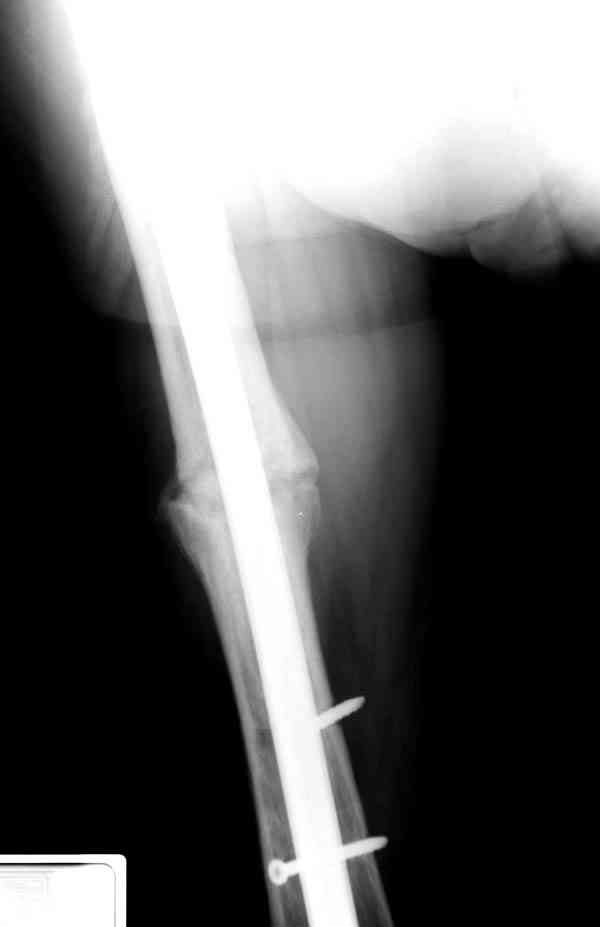

Уважаемые коллеги! У пациента 50-ти лет ложный сустав голени, перелом интрамедуллярного штифта. Перелому около 2 лет, ходить с полной нагрузкой начал через 3 мес. после операции. Боли при ходьбе почувствовал около 2 мес. назад. На данный момент ходит с полной нагрузкой без посторонней опоры. Среди коллег развернулась дискуссия по поводу способа оперативного лечения: -удаление штифта с перештифтовыванием блокированным штифтом с рассверливанием и остеотомией м\б кости -стабилизация зоны ложного сустава по медиальной поверхности LCP-пластиной с декортикацией или без -удаление штифта или без и синтез в АВФ с декотрикацией или без и остеотомией м\б кости

уважаемый коллега! Здесь имеется типичный тугой ложный сустав б/берцовой кости. У нас бы удалили старый стержень, реостеосинтез более толстым стержнем с рассверливанием с блокированием в динамическом варианте. Проблема будет с удалением дистального отломка стержня. Здесь на форуме это вопрос уже рассматривался неоднократно. Поищите по поисковику.Вот здесь, кажется http://weborto.net/forum/1164105478/, http://weborto.net/forum/1192794837

Все перечисленные варианты способны привести к желаемому результату. Несращение здесь - результат нестабильности, так что любой вариант

стабилизации решит проблему. Одного безоговорочно лучшего нет, у всех есть плюсы-минусы.

Наименьший по инвазивности - наложение спицевого аппарата без удаления стержня, с последующей либо дистракцией либо компрессией. Можно и устранить антекурвацию, это тоже создаст стабилизирующее напряжение тканей.

Наиболее быстро достичь опорности без боли и внешних приспособлений - удаление и блокируемый реостеосинтез с рассверливанием. Лучше бы тоже с

восстановлением оси (отклоняющая спица в дистальном отломке, чтобы новый стержень прошел не в старый канал, а кзади от него), еще и для создания дополнительного напряжения тканей в области несращения. Открывать зону несращения не надо.

Сросшаяся малоберцовая как распорка привела к образованию ложного сустава. В таких случаях удаляем сломанный штифт и проводим стимуляцию ложного сустава рассверливанием. Рассверливание канала создает стимуляцию на месте ложного сустава, и динамический вариант блокировки штифта с большим диаметром создаст стабильность. Ранняя нагрузка после остеотомии малоберцовой приведет к сращению ложного сустава.